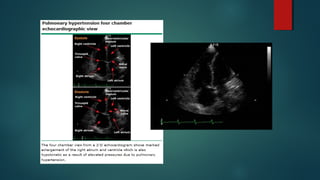

ECOCARDIOGRAMA

 Debe solicitarse siempre ante sospecha de HP.

 Utilidad:

 Estimación de la Presión de la Arteria Pulmonar.

 Tamaño del VD.

 Tamaño de la AD.

 Función Sistólica y Diastólica.

 Función Valvular (principalmente insuficiencia tricuspidea)

 Shunt Intracardiacos.

ECOCARDIOGRAMA  Debe solicitarsesiempre ante sospecha de HP.  Utilidad:  Estimación de la Presión de la Arteria Pulmonar.  Tamaño del VD.  Tamaño de la AD.  Función Sistólica y Diastólica.  Función Valvular (principalmente insuficiencia tricuspidea)  Shunt Intracardiacos. Lewis J Rubin, MD et al. «Clinical features and diagnosis of pulmonary hypertension in adults”. UPTODATE. Literature review current through: May 2015.